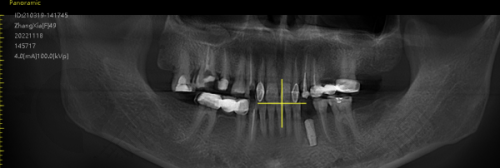

中诺口腔医院在种植牙技术方面实力强劲。医院配备有口腔全景片健康检查设备、种植专用手术室及数字化导板系统。主打“即刻种植”“全口种牙”“当天种牙”三大核心优势,支持微创种植、复杂骨缺损种植、前牙美学区种植修复等高难度技术。

特别值得一提的是“立得用”种植体系,通过多学科联合诊疗,实现“当天种牙当天用”的快速修复结果,深受患者好评。医生团队会根据患者的具体情况,如牙槽骨条件、牙齿缺失情况等,制定个性化的种植方案。例如,对于牙槽骨条件不好的患者,会先做植骨或上颌窦提升,再进行种牙,术后修复更快,种出来的牙齿也更稳固。